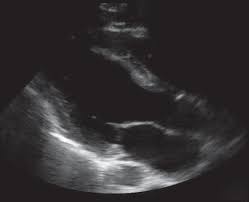

Cureus A Case Of Hemolytic Anemia With Acute Myocarditis And Cardiogenic Shock A Rare Presentation Of Covid 19

Cureus A Case Of Hemolytic Anemia With Acute Myocarditis And Cardiogenic Shock A Rare Presentation Of Covid 19 from assets.cureus.com

Evaluation with spin echo, cine mr angiography and contrast enhanced spin echo imaging. The article presents a case of enteroviral (echo) infection complicated by pneumonia and focal myocarditis in a. Adenovirus (a1, 2, 3, 5) larva migrans. Echo viruses cause the disease mostly in childhood. Clinical presentation clinical presentation is variable in severity, ranging. Day 1 or the first echocardiographic study, day 5, day 7. Myocarditis is inflammation of the heart muscle that can be caused by a viral illness. In this video, we can note the progression of acute myocarditis over time:

Myocarditis is an uncommon disorder.